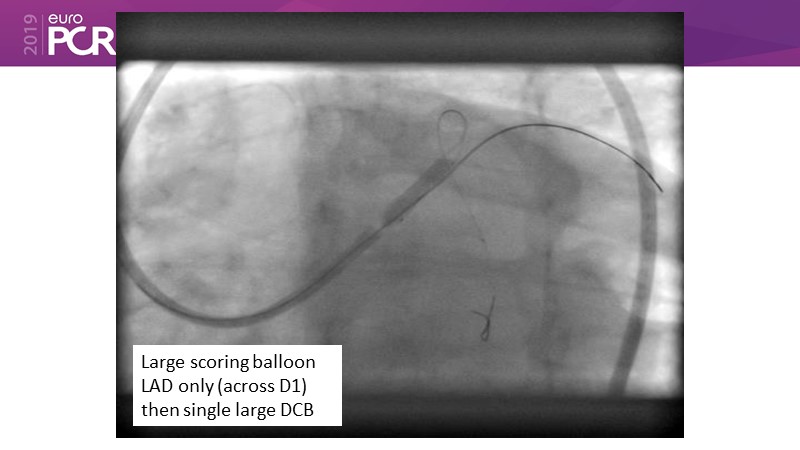

Go implant-free in de novo lesions: DCB-only strategy

Consult this session to learn about the DCB-only concept, treatment methodology and consensus group recommendations, and discover the latest scientific evidence of DCB-only in de novo lesions and in complex PCIs.